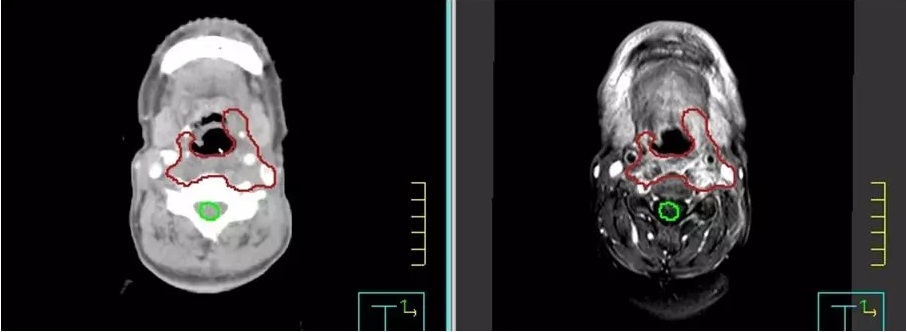

CT+MRI采用深度神经网络在肿瘤靶区自动勾画出放疗靶区,该技术提高了人工勾画的效率。

放疗前,医生需要勾画出肿瘤的精确范围,同时要勾画出需要保护的正常组织的范围,这一步骤的质量决定了放疗质量的60%。而现行的方案一般都是由放疗医生人工勾画,没有统一的勾画标准,不同的医生之间勾画的结果差异较大,增加了许多不确定性。